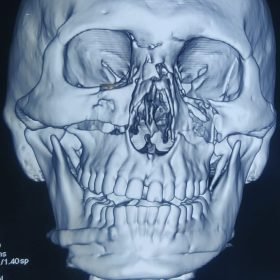

Orthognathic Surgeries

Jaw surgery, is a procedure that corrects jaw abnormalities. The goal is to improve the appearance of jaws.

Maxillofacial Surgeries

Maxillofacial procedures can treat diseases, fix injuries in your face.